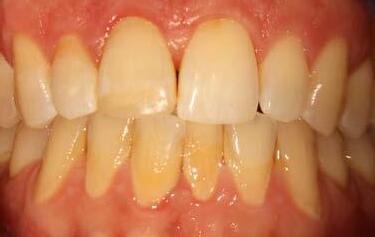

This is not a “Terminal Dentition”. It is interesting to see the increase in patients being advised that Periodontitis is not treatable or that treatment is somehow expensive and ongoing maintenance is difficult/unachievable. These patients are usually advised to receive implant treatment as an alternative.

This patient first presented in 2016 at the age of 33 years. He was a former smoker (quit two years prior to the initial presentation). He presented with generalised deep pocketing and advanced loss of attachment.

The patient had orthodontic treatment between 2018-2020 to address the flaring and spacing of his teeth, which was a cosmetic concern to him (orthodontic treatment done by Dr Frank Furfaro). Long-term evidence shows that we, as dental clinicians, are not accurate at determining the prognosis of periodontally compromised teeth (McGuire 1996). We may also be hasty at labelling such teeth as “hopeless”. The threshold at which we

The patient was managed with non-surgical periodontal debridement. Two months later, he presented with an encouraging reduction in periodontal probing depth (PPD). There were 85% sites with PPD 1-3mm, 15% sites with PPD 4-5mm and no sites with residual PPD > 6mm. The patient showed excellent plaque control measures and his bleeding on probing score was 1%. The patient has been placed on a six-monthly periodontal maintenance program with the periodontist. He also sees his general dentist once annually. The OPG images dated 2016 and

decide to extract teeth due to periodontal disease may be too low (Splieth 2002). There is no evidence on the other hand that dental implants have longer survival or less complications or better cost compared to periodontally treated teeth.